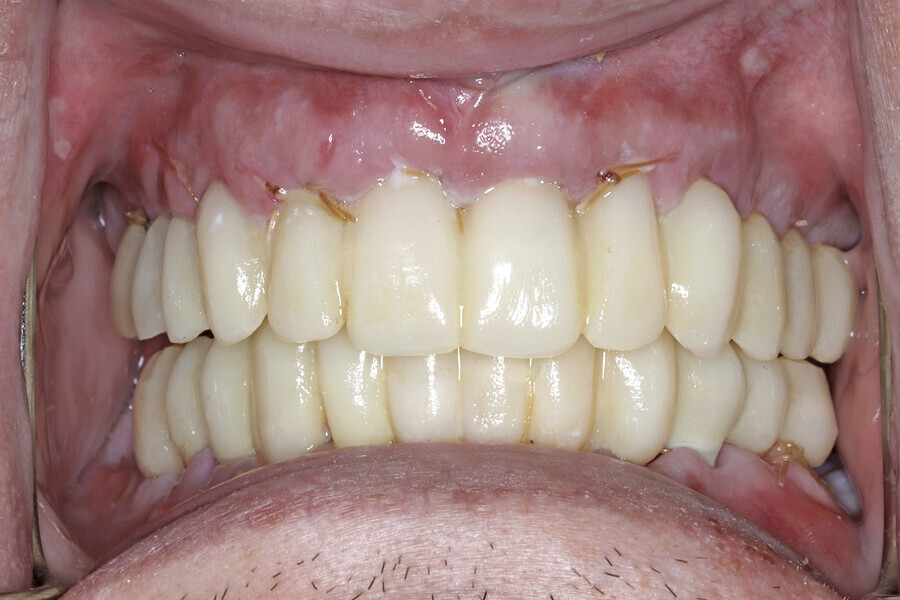

Fig. 17b: Retracted intra-oral view.

Fig. 17c: Final patient smile showing excellent aesthetics and a happy patient.

The final restorations were passively and accurately seated ten days later uneventfully using Vortex LA VIS screws. Confirmation records were taken with photographs, radiographs and digital articulation to recheck fit, function, phonetics and occlusion (Fig. 17a). The patient was extremely satisfied with his final restorations, describing the process as life-changing and surprisingly fast in comparison with what he had heard about full-mouth implant therapy. He was especially pleased with the speed at which the final process was able to be completed (Figs. 17b & c).